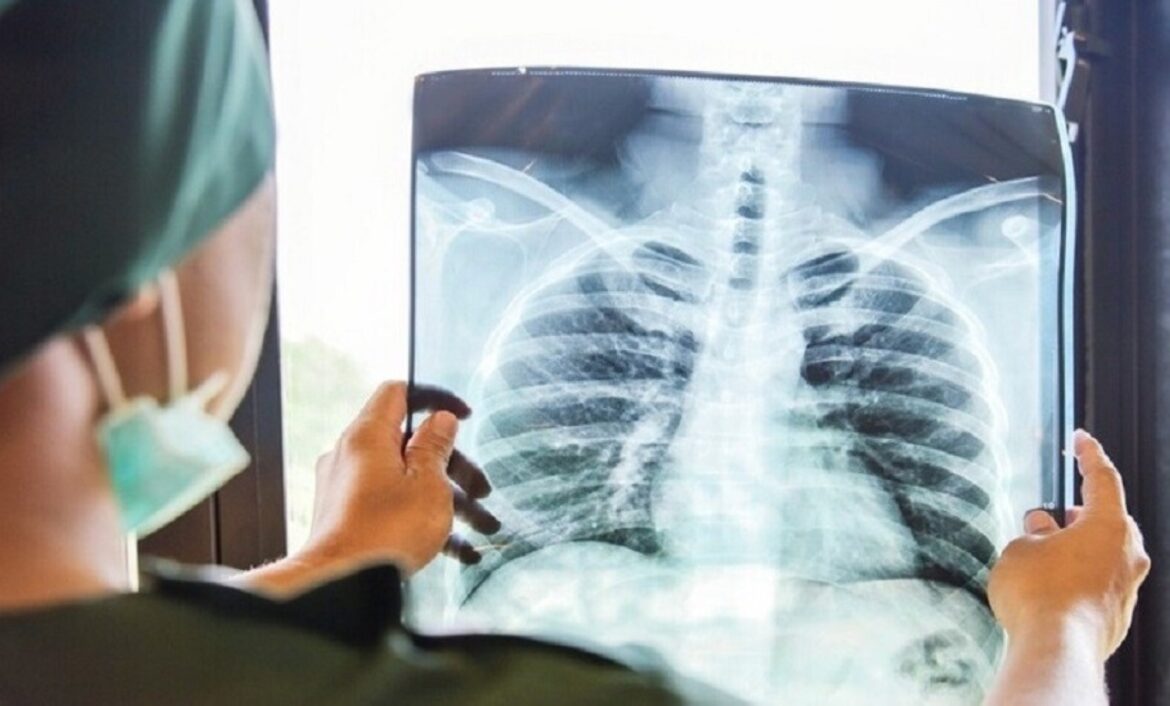

كشفت مدينة الملك فهد الطبية، أن السُعال الديكي يُعَدّ مرضًا بكتيريًا مُعديًا يصيب الجهاز التنفسي، وينتقل عبر الرذاذ المتطاير عند السعال أو العطاس، مؤكدةً أهمية التعرف المبكر على أعراضه واتباع الإرشادات الوقائية للحد من انتشاره، لا سيما بين الفئات الأكثر عُرضة للمضاعفات.تبدأ برشح في الأنف واحتقان بالحلقوبيّنت المدينة الطبية أن أعراض السُعال الديكي تبدأ غالبًا برشح في الأنف واحتقان بالحلق، مع ارتفاع في درجة الحرارة وشعور بالتعب والإرهاق العام، قبل أن تتطور الحالة إلى سعال شديد ومتواصل قد يزداد حدّة مع الوقت، ويكون مصحوبًا بنوبات سعال متتابعة تؤثر في التنفس والنوم.وأضافت أن الفئات الأكثر عُرضة للإصابة تشمل الرضّع والأطفال دون عمر السنة، والنساء الحوامل، والأشخاص غير المطعّمين، إضافة إلى المخالطين المباشرين لشخص مصاب، مشددة على أن التطعيمات الدورية تمثل خط الدفاع الأول للوقاية وتقليل شدة المرض.وحول العلاج، أشارت إلى أن التدخل الطبي يعتمد على استخدام المضادات الحيوية المناسبة، إلى جانب تقديم العناية التنفسية اللازمة للحالات المتقدمة، مع متابعة وظائف القلب والرئتين عند الاشتباه بارتفاع ضغط رئوي، مؤكدة أن الالتزام بالخطة العلاجية والمتابعة الطبية يسهمان في تقليل المضاعفات وتسريع التعافي.

ينتقل عبر الرذاذ المتطاير عند السعال أو العطاس